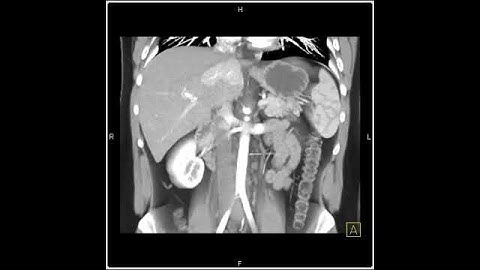

Abdomen: Liver: 3D Mapping with a range of rendering techniques(3 of 3)